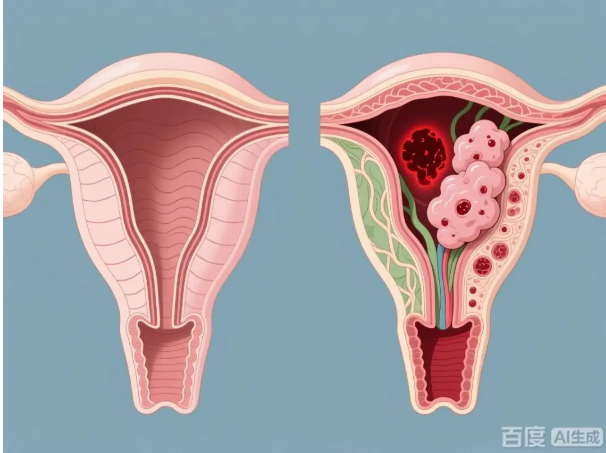

子宫腺肌症,是指子宫内膜的腺体和间质侵入子宫肌层生长所形成的病变。简单来说,就是本该待在子宫腔内的内膜组织,跑到了子宫肌肉层里“安家”。

这些“安错家”的内膜组织,同样会随着月经周期发生增生、脱落和出血。但不同于正常的经血可以排出体外,这些在肌层内的出血无法排出,因而刺激周围肌肉组织,引发一系列问题:

可以将子宫腺肌症的病灶理解为一个需要血液供应才能生长和引起症状的组织。介入治疗通过向供养病灶的血管内注入微小的栓塞颗粒,从而减少或阻断其血液供应。血液供应减少后,病灶因缺乏养分而逐渐萎缩、纤维化,相关症状也因此可能得到缓解。